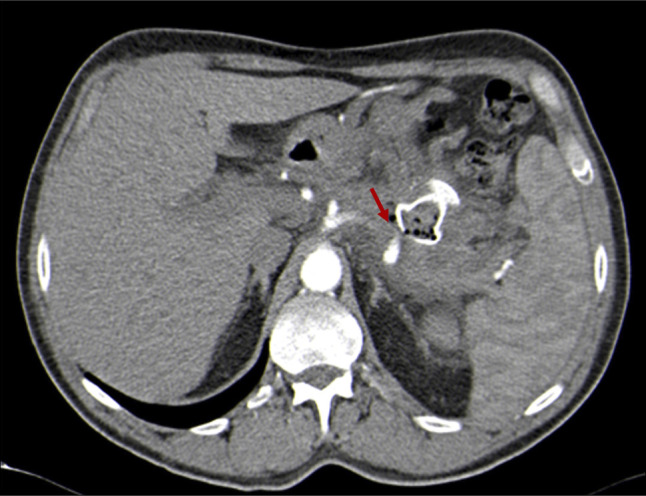

管腔旁置金属支架(LAMS)已被用于胰周收集物的引流,尽管它们可能伴有并发症,包括出血。我们报告一个49岁的男性病人,他出现呕血和晕厥后三周半的LAMS放置胰腺周围收集引流。计算机断层扫描显示脾动脉被支架远端法兰侵蚀。切除LAMS前行脾动脉栓塞术,3天后行脾切除术。患者在两年的随访后仍无症状。本病例展示了一种治疗罕见但可能致命的LAMS并发症的方法。

Lumen-apposing metal stents (LAMS) have been used for drainage of peripancreatic collections, although they may be associated with complications, including bleeding. We report a case of a 49-year-old male patient who developed hematemesis and syncope three and a half weeks after LAMS placement for peripancreatic collection drainage. A computed tomography scan revealed splenic artery erosion by the distal flange of the stent. Splenic artery embolization was performed before LAMS removal, and splenectomy was required 3 days later. The patient remains asymptomatic after two years of follow-up. This case demonstrates an approach to a rare but potentially fatal complication of LAMS.